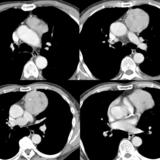

Case 8c Thymoma CT

Date: 03/27/2009

Views: 15482